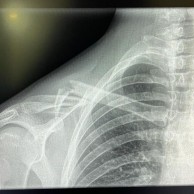

La campeona de España XCO sufrió una dura caída al inicio de la Copa del Mundo de Lenzerheide y su evacuación del circuito hacia el hospital ya hacía prever que podía tener alguna lesión de cierta importancia. Finalmente se ha confirmado que sufre una rotura de la clavícula derecha.

Tras evacuarla del circuito, el primer diagnóstico en el hospital suizo dejó claro que la española sufre una rotura de clavícula derecha y será trasladada a Madrid para ser operada en los próximos días operada el martes 23 de junio por el Dr. Esparza en Murcia.